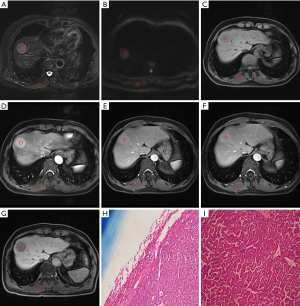

There was a statistically significant correlation between RCR and small HCC in arterial phase images (ρ=−0.305, P<0.05). In terms of multiple comparisons, the RCR of the small PD HCCs was significantly lower than that of the small WD HCCs (P<0.05), whereas no significant difference existed between small WD HCCs and MD HCCs (P=0.083) (Figures 3,4), or between small MD HCCs and PD HCCs (P=0.076).

This study demonstrated that the correlation between RCR and small HCC in arterial phase images is statistically significant. There was a significant difference in the RCR between well- and PD HCCs, though not among other histological grade combinations. In previous studies regarding intravoxel incoherent motion, the perfusion fraction has been shown to be positively correlated with the contrast agent enhancement ratio in the arterial phase (30). In our study, the mean arterial phase RCR of WD HCCs tended to be higher than that of other histological grades.